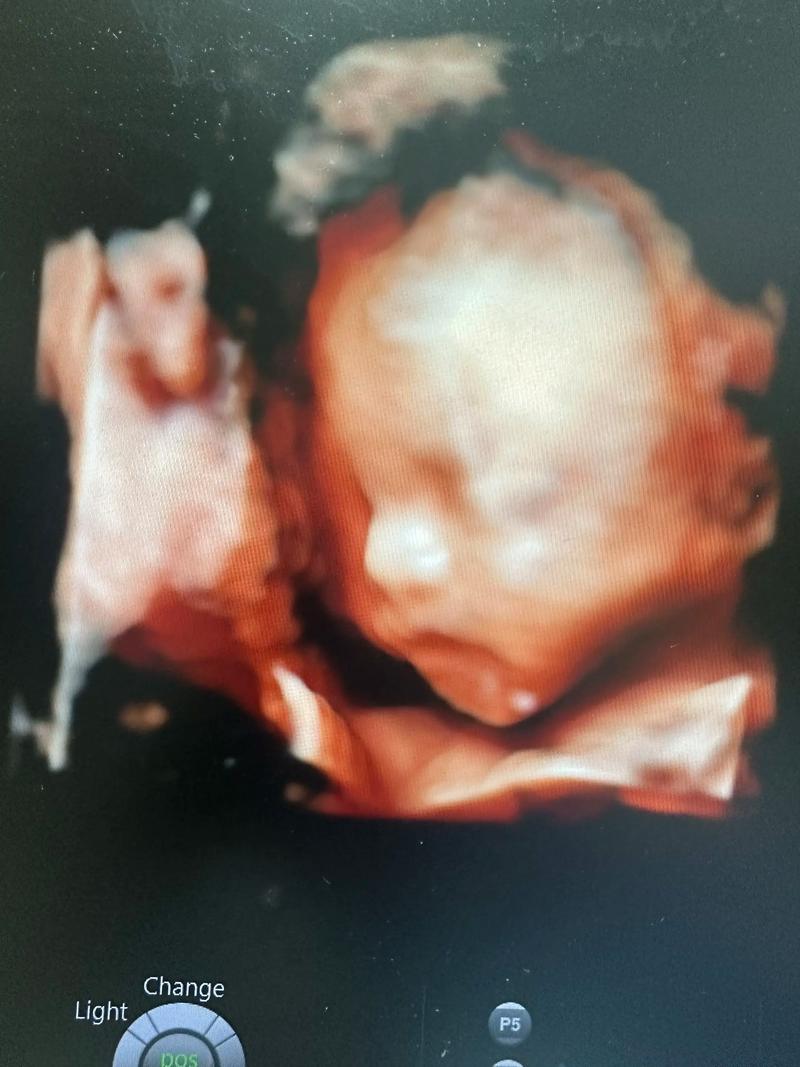

四维彩超(也就是系统超声筛查)的核心目的是“排畸”,即筛查胎儿是否存在结构上的异常,胎儿的生长发育是一个动态的过程,不同的器官在不同的孕周有不同的发育特征和最佳观察时机,在不同时间点进行检查,可以各有侧重,互相补充。

这是最重要、最全面、最经典的一次系统超声筛查,也是绝大多数孕妇口中所说的“大排畸”检查。

- 面部结构: 清晰地观察胎儿的颜面部,包括眼、鼻、口、唇,是诊断唇腭裂的黄金时期。

- 心脏结构: 这是本次检查的难点和重点,需要系统地观察胎儿心脏的四个腔室、两大动脉、房室间隔、瓣膜等,筛查先天性心脏病,这个时期胎儿心脏大小适中,羊水量适中,是观察心脏的最佳时机。

意义: 这次检查是对胎儿全身结构进行的一次“地毯式”的详细排查,是发现绝大多数胎儿结构异常的关键时期。